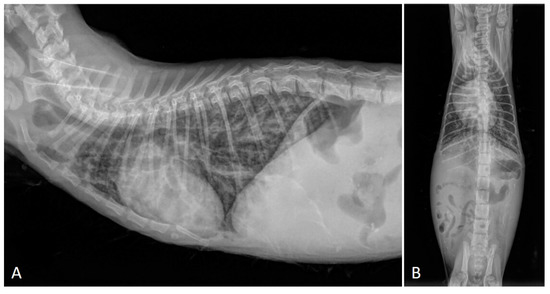

2.2. Radiographic Findings

- Febo, E.; Crisi, P.E.; Traversa, D.; Luciani, A.; Di Tommaso, M.; Pantaleo, S.; Santori, D.; Di Cesare, A.; Boari, A.; Terragni, R.; et al. Comparison of clinical and imaging findings in cats with single and mixed lungworm infection. J. Feline Med. Surg. 2019, 21, 581–589. [Google Scholar] [CrossRef]

- Genchi, M.; Ferrari, N.; Fonti, P.; De Francesco, I.; Piazza, C.; Viglietti, A. Relation between Aelurostrongylus abstrusus larvae excretion, respiratory and radiographic signs in naturally infected cats. Vet. Parasitol. 2014, 206, 182–187. [Google Scholar] [CrossRef]

- Lacava, G.; Zini, E.; Marchesotti, F.; Domenech, O.; Romano, F.; Manzocchi, S.; Venco, L.; Auriemma, E. Computed tomography, radiology and echocardiography in cats naturally infected with Aelurostrongylus abstrusus. J. Feline Med. Surg. 2017, 19, 446–453. [Google Scholar] [CrossRef]

- Dennler, M.; Bass, D.A.; Gutierrez-Crespo, B.; Schnyder, M.; Guscetti, F.; Di Cesare, A.; Deplazes, P.; Kircher, P.R.; Glaus, T.M. Thoracic computed tomography, angiographic computed tomography, and pathology findings in six cats experimentally infected with aelurostrongylus abstrusus. Vet. Radiol. Ultrasound 2013, 54, 459–469. [Google Scholar] [CrossRef]